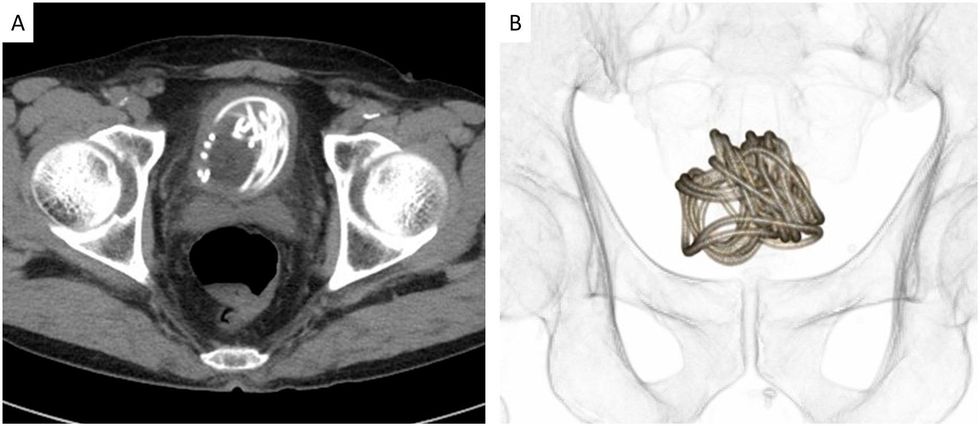

After various scans, doctors discovered "a large object accompanied by acoustic shadows", which they later learnt to be "an intricately entangled jump rope in the bladder".

Once doctors established the foreign object, they went on to remove the rope after deeming endoscopic surgery unsuitable.

Given the large length of the rope and its placement in the bladder, the extraction was unsurprisingly difficult.

"Traditionally, grasping forceps and retrieval baskets are used to remove foreign bodies," said Professor Toshiki Kijima, co-author of the study. "However, wires inserted into the bladder usually curl up as the bladder contracts; therefore, special consideration is required for wire-like foreign bodies."